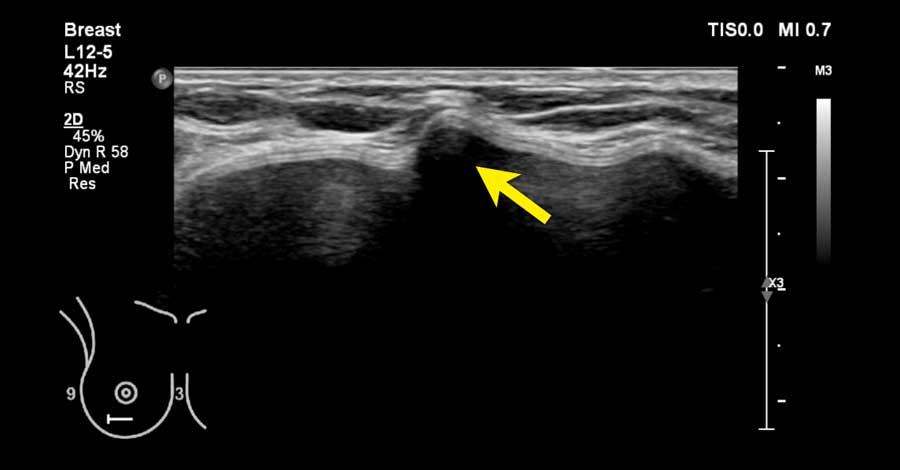

Khi quan sát đường bờ của mô tuyến (mũi tên), có thể hình dung rằng khi sờ nắn sẽ cảm thấy gồ ghề và đôi khi tạo cảm giác như có một khối u khi mô tuyến rất phát triển.